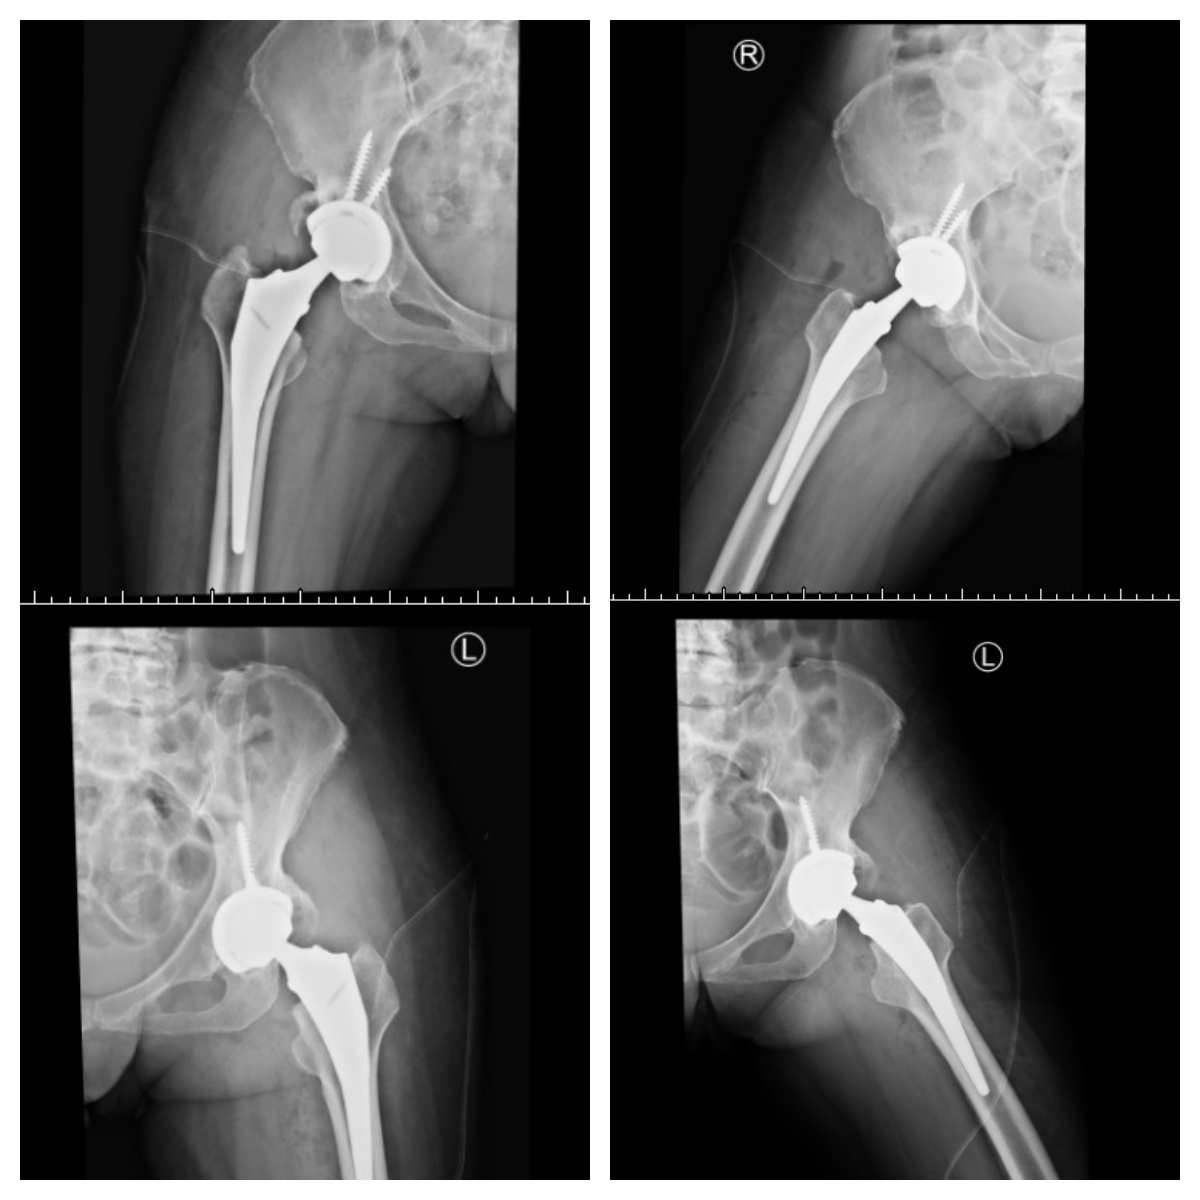

圖說:香港女性病患雙側髖關節手術順利。(圖片來源: 七賢脊椎外醫院提供)

來自香港62歲的阮女士,受雙髖疼痛折磨多年,且復健效果不符期待,讓疼痛不已的她難以忍受。家人及友人不捨阮女士承受如此大的痛苦,帶她跨海至高雄七賢脊椎外科醫院求診並安排進行手術。

在院長黃旭霖帶領下,七賢脊椎外科醫院預計明年準備引進羅莎電腦導航人工正前開髖關節手術,期許成為高雄第一間髖膝人工智能導航手術醫院。楊華偉表示,正前開人工髖關節手術好處多,不破壞肌肉,恢復快,平躺手術病患舒服且長短腳好控制。